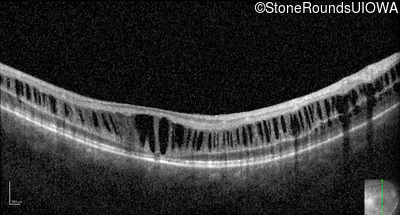

Optical Coherence Tomography - Right - 10/40

Exemplar / OCT Stack